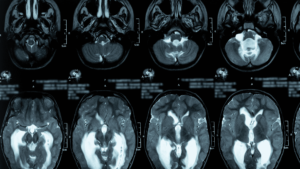

O diagnóstico é confirmado pela neuroimagem. A **Ressonância Magnética (RM) de Crânio** revela o achado característico de ventrículos cerebrais aumentados (hidrocefalia) desproporcionais ao grau de atrofia cerebral (perda de tecido). A presença de achados específicos na RM, como o fluxo aumentado do LCR na região do aqueduto, também reforça a suspeita.